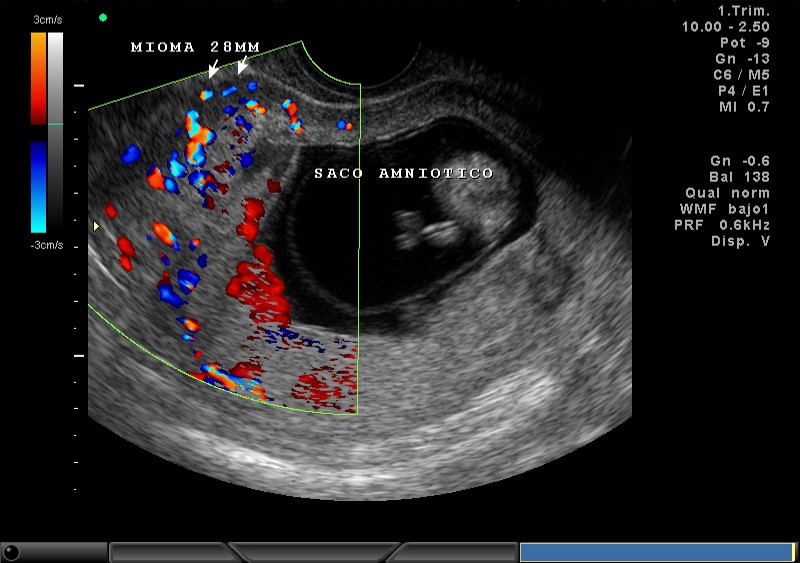

2D Y COLOR, PLACENTA, MIOMA